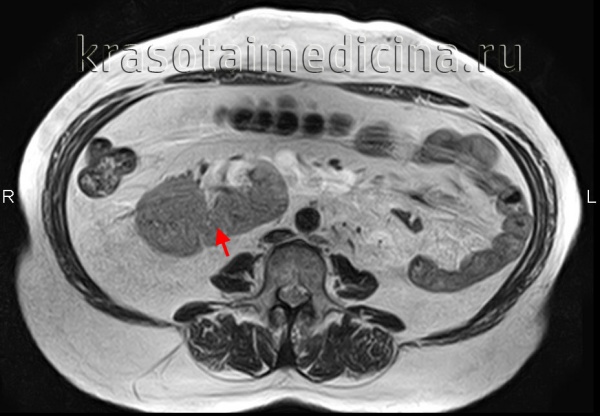

МРТ почек. Аксиальная Т2-ВИ. Подковообразная почка.

3. МРТ при эктопии почки плода:

• Прибегают в случае затруднительной диагностики:

о Позволяет отличить эктопическую почку от кишечника

о Помогает отличить почечную паренхиму от солидного или кистозного образования малого таза